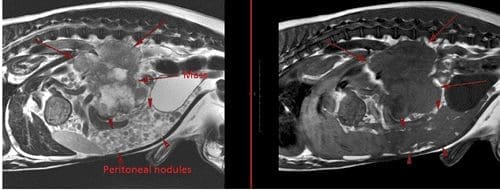

MRI showed widespread peritoneal nodules on a much more dramatic scale than suggested by ultrasound and in addition identified the presence of pulmonary nodules (likely mets) which had not shown up on inflated chest radiographs. The MRI was able to tell us that the mass was most likely originating from the right adrenal gland and was inoperable.